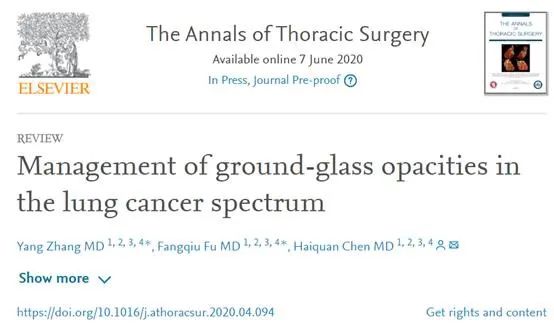

“磨玻璃”结节型肺癌诊治有了“复旦标准” :早期“纯磨玻璃肺癌...

“磨玻璃”结节型肺癌诊治有了“复旦标准” :早期“纯磨玻璃肺癌...